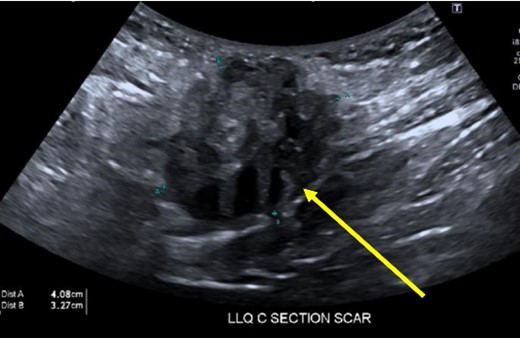

A 38-year-old female with past medical history of hypertension, migraine headaches, and anemia as well as past surgical history of two Cesarean sections presented to our general surgery clinic with a painful abdominal mass at the left lateral aspect of her Pfannenstiel incision. She reported that her most recent Cesarean section was 4 years ago with recurrent pain over the incision for about 2 years. Of note, 2 years prior to presentation at our clinic, she was seen by a general surgeon for similar symptoms and was found to have two subcutaneous nodules at the lateral edge of the Pfannenstiel scar. Ultrasound of the region at that time showed two hypoechoic, nonvascular, and non-fluid-filled subcutaneous nodules suggestive of suture granulomas (Fig. 1). Since then, she had experienced intermittent discomfort. More recently, each month at the time of menstruation, she stated that the mass would enlarge and become more painful. After menstruation, the mass would decrease in size and the pain would recede. On this visit, ultrasound revealed a heterogeneous vascular soft tissue mass measuring 4.1 × 3.3 × 4.4 cm, suspicious for endometrioma in the setting of her clinical history (Fig. 2).

Hypoechoic, nonvascular, non-fluid-filled subcutaneous nodule (arrow), likely suture granuloma.

It is interesting to note that our first patient’s complaints began 2 years prior to presentation in the form of two subcutaneous nodules found in the same region as the present mass. These nodules were diagnosed as suture granulomas, a common misdiagnosis for endometrioma. The onset of suture granuloma ranges from days to years after surgery and varies in clinical presentation [13]. It can be removed surgically or it can spontaneously resolve. Ultrasonography of a suture granuloma has a characteristic hyperechoic single or double line within a hypoechoic lesion [14]. The patient’s original ultrasound at that time revealed hypoechoic nodules, though without mention of hyperechogenicity within the lesion. On clinical examination, the lesion resembled a suture granuloma. It is currently unclear whether or not these lesions were related to the endometrioma, a localized tissue reaction to newly implanted endometrium, or suture granuloma only. Regardless, incisional pain in the setting of previous uterine surgery warranted further evaluation to rule out endometriosis [15].